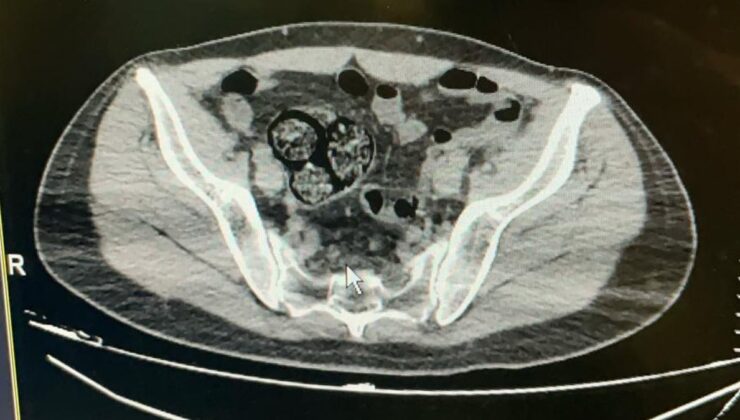

Artvin Devlet Hastanesi’ne götürülen F.R.’nin yapılan tomografisinde, bağırsaklarında 10 paket uyuşturucu madde taşıdığı belirlendi.

Şüphelinin hayati tehlike oluşturabilecek şekilde sakladığı paketler cerrahi müdahale ile çıkarıldı.